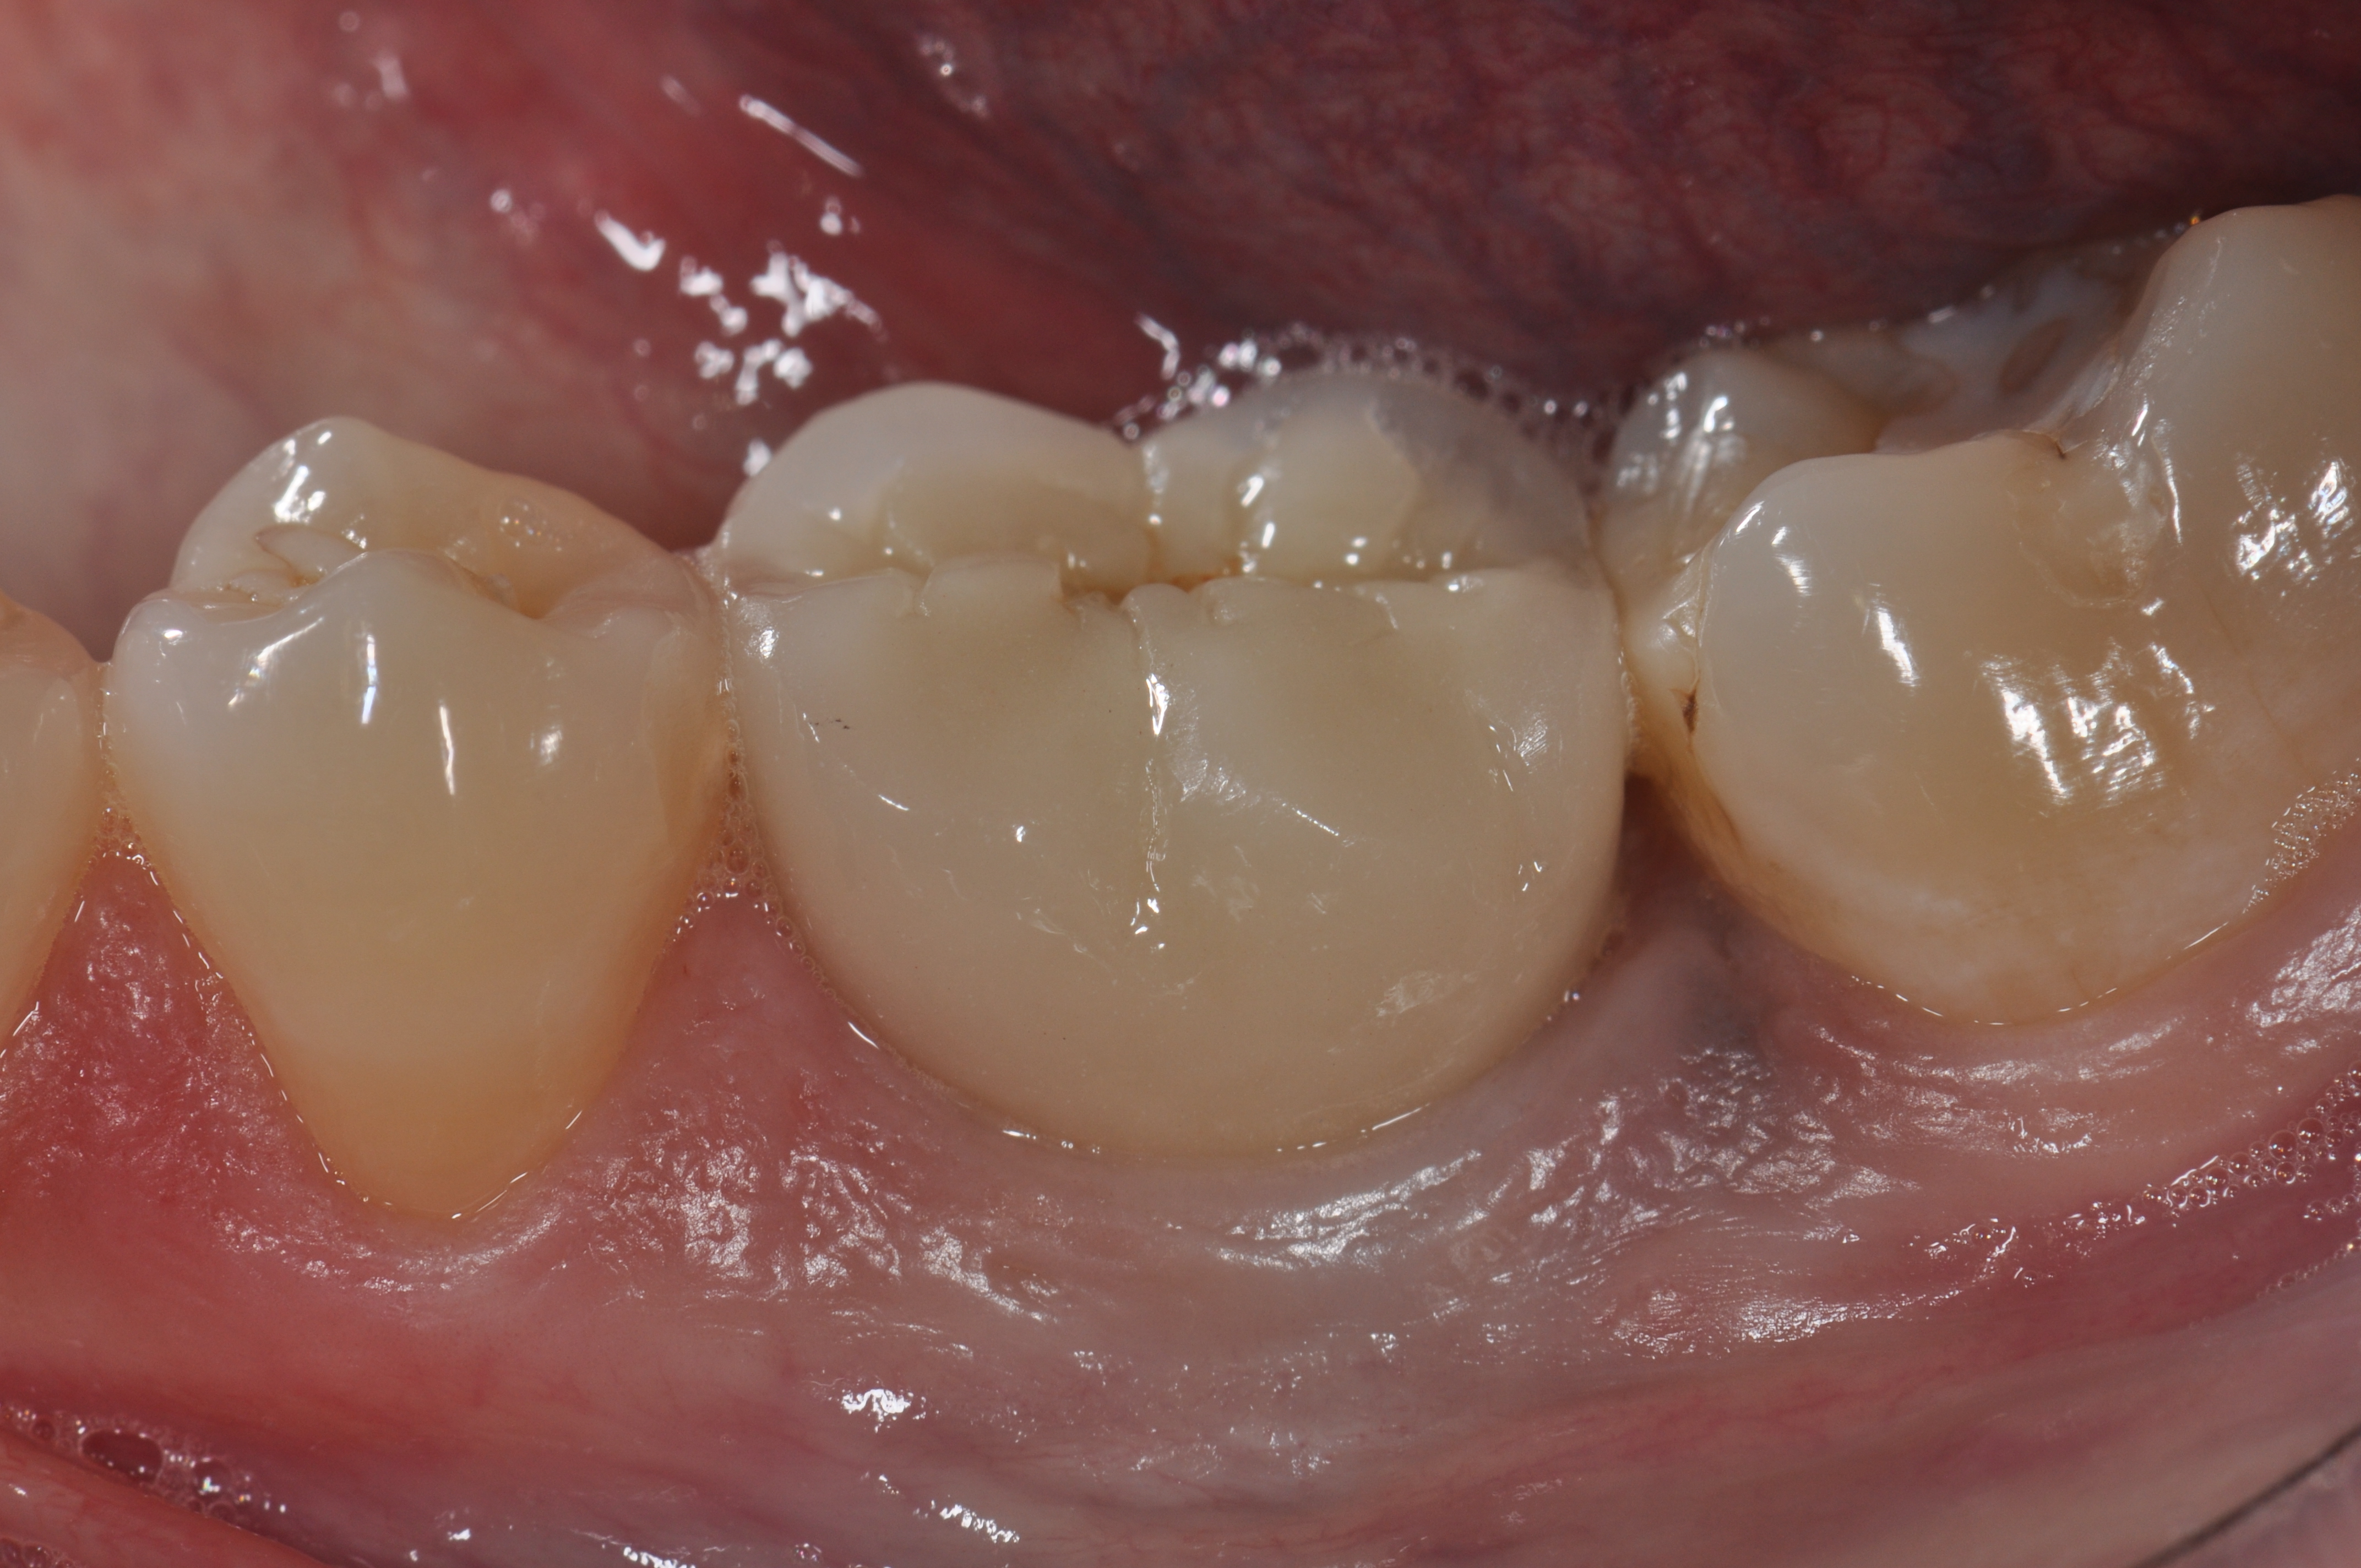

Fig 6. A clinical view of this area suggests that peri-implant mucositis is present. The tissue is swollen, it bleeds on probing, has 5 mm of probing depth, and exhibits purulent exudate.

Figure 6

Fig 7. Eight weeks after nonsurgical treatment that involved scaling of the area, which removed cement, and irrigation with an anti-inflammatory hydrogel, the area is healthy. No BOP is present, purulence is absent, and probing depths have been reduced to 4 mm as a result of the reduction in inflammation.

Figure 7